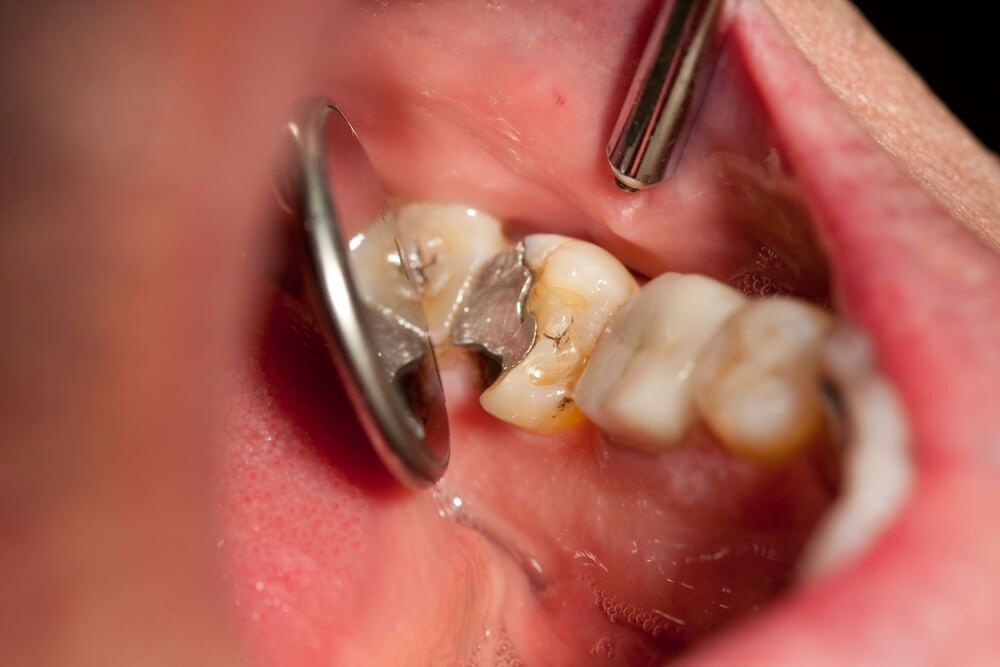

Cavities are pretty common. As the National Institutes of Health points out, the only condition more common than a cavity is the common cold. If you've never experienced tooth decay, you might wonder, "What does a cavity feel like?" The answer depends on the stage of the cavity and what foods you eat. Some foods, such as sweets, might trigger the pain of a cavity more than others.

How Cavities Form

Your mouth is naturally full of germs. Some of those germs are perfectly healthy, but others can be harmful. When you eat something sugary, such as candy or even potato chips, or drink a sugary beverage, the germs feed on the sugars in the substance. This produces acid, which is strong enough to wear away tooth enamel if not cleaned off quickly enough. In the end, a dental cavity begins to form.

In the early stages, a cavity can be reversed, as the National Institute of Dental and Craniofacial Research notes. Brushing your teeth with a toothpaste that contains fluoride can help restore the enamel and reverse the effects of cavities.

Signs of a Cavity

What does a cavity feel like? In the earliest stages, the answer might be nothing. There are no nerves in your tooth enamel, so when the decay is in that layer, you likely won't feel a thing. Once the decay has progressed enough to reach the softer tissues inside the tooth, where the dentin and nerves are, you might notice signs of a cavity. Your teeth might feel sensitive and you could feel some pain, especially after eating sweets, hot foods or cold foods. The pain can be fairly mild or sharp and intense. Some people with cavities also feel pain when biting down.

Depending on the size of the cavity, you may be able to see evidence of it in your mouth. Cavities sometimes create visible holes in the teeth. They can also create stains that are black, brown or white on the surface of the tooth.

Cavities and Sweets

Why are you more likely to feel pain from a cavity when you eat sweets? Some foods, including sweets, are more likely to cause pain when there is enamel erosion. Sweet foods tend to be sticky, so they often cling to your teeth. The germs that feed on them can then produce more acid, which can make its way into the cavity, irritating the nerves. Even if you don't have a cavity, sugary foods will cause more sensation in sensitive teeth.

Seeing Your Dentist

What should you do if you think you have a cavity? The first step is to see your dentist. Although cavities can be reversed in the early stages, by the time you are feeling discomfort or pain, only a dentist can treat them. An x-ray will be taken to determine how the cavity has progressed into the tooth. Depending on how severe the cavity is, you might need a filling to fix it. If the decay is very severe, the dentist might replace the tooth with a crown or perform a root canal.

Even if you're not sure if you have a cavity, regular professional cleaning and dental visits are important. A dental hygienist can apply a fluoride treatment to help strengthen the teeth and reverse the very early stages of decay. He or she can also give you tips on the best ways to brush your teeth and advise you about what foods to avoid or consume less frequently to reduce your risk for cavities. As with many conditions, when it comes to cavities, taking preventative steps is a lot easier than treating the problem down the road.